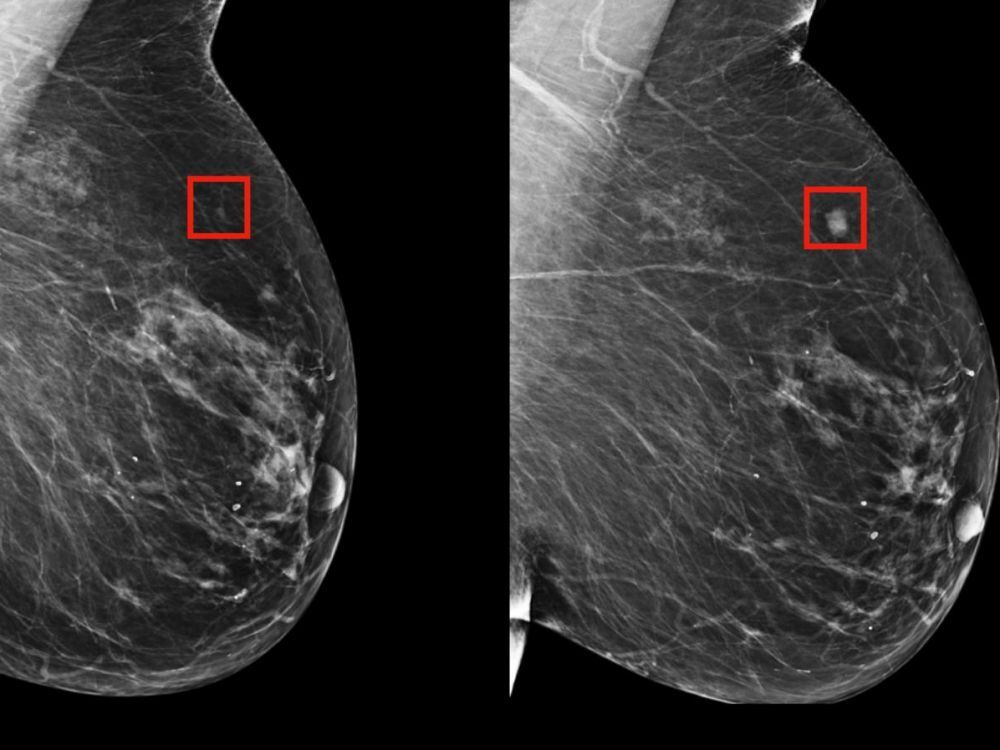

LE CANCER DU SEIN